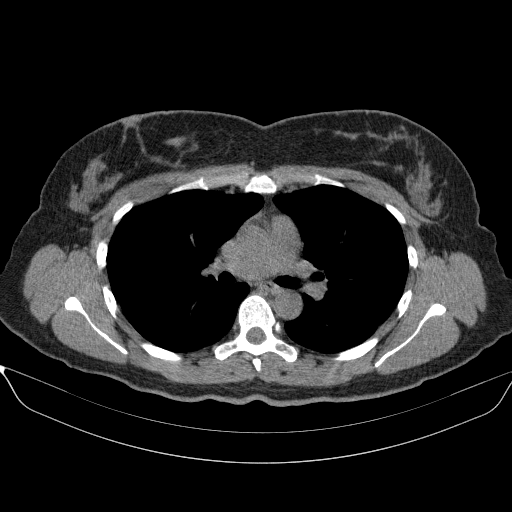

Generated VENOUS CT scan (A→B translation)

Full window (WL 1023.5, WW 4095 β†’ Low βˆ’1024, High +3071)

Lung window (WL -600, WW 1500 β†’ Low βˆ’1350, High +150)

Mediastinum window (WL 40, WW 400 β†’ Low βˆ’160, High +240)